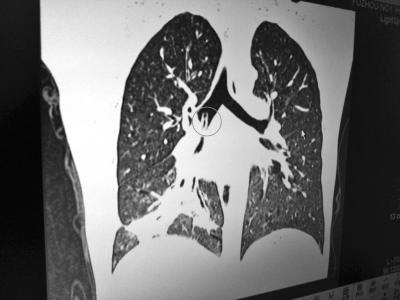

CT显示肺部有异物(画圈处)

医生初步检查发现小文的胸部有杂音。通过影像学进一步检查,发现小文的肺部有异物。在询问之后,发现小文有异物吸入史,医生怀疑这个异物很有可能就是小文“吞下”的口哨。